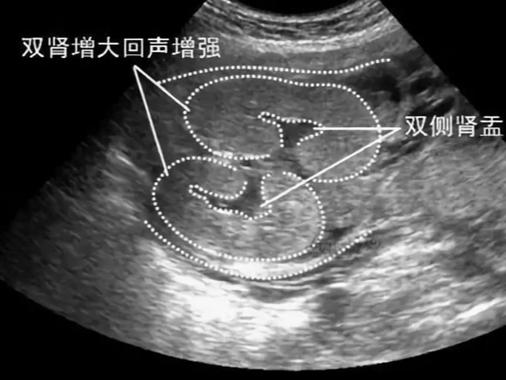

- 肾集合系统:可以理解为肾脏里的“排水系统”,包括肾盏、肾盂,它们负责收集肾脏过滤出来的尿液,然后输送到输尿管。

- 分离:在B超图像上,这些“排水管道”因为里面存有尿液而显得扩张、变宽,就像一根水管里充满了水,管腔就变大了。

“双肾集合系统分离”就是指在B超下,双侧肾脏的肾盂或肾盏都出现了轻度的扩张。